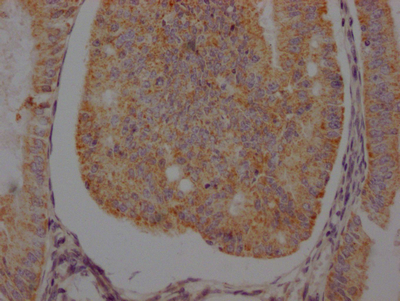

CSB-RA286054A0HU

IHC image of CSB-RA286054A0HU diluted at 1:100 and staining in paraffin-embedded human prostate cancer performed on a Leica BondTM system. After dewaxing and hydration, antigen retrieval was mediated by high pressure in a citrate buffer (pH 6.0). Section was blocked with 10% normal goat serum 30min at RT. Then primary antibody (1% BSA) was incubated at 4℃ overnight. The primary is detected by a Goat anti-rabbit IgG polymer labeled by HRP and visualized using 0.05% DAB.